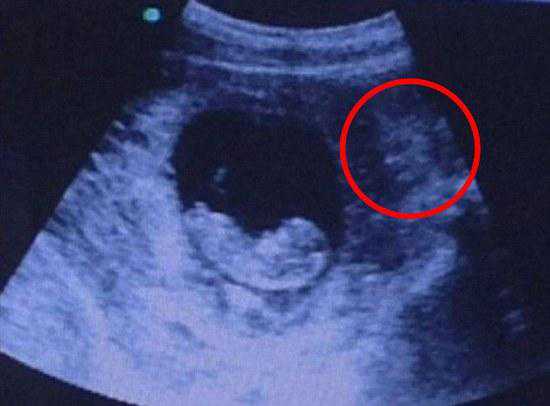

原来这张超声波照片,看上去有一只酷似猫的东西正注视着子宫内的胎儿,这就让人毛骨悚然了,一下子联想到古代“狸猫换太子”的说法,虽然没什么科学依据,但老人家觉得这个孩子不吉利、要不得,硬是要章女士打掉孩子,章女士觉得这纯属无稽之谈,自己好不容易怀上的宝宝哪能说不要就不要!

从医学角度看,宝宝处在不断发育和运动中,宝宝周围的胎盘组织(羊膜、叶状绒毛膜和底蜕膜)会随着胎儿的运动发生位置改变,在加上拍照角度的影响,所以才会拍出恐怖的象形化胎儿照片。为此幸孕姐特意收集了以下会让父母心情一下从天堂掉到地狱的恐怖超声波照——

照片中,胎儿已初具人形,而右上角的胎盘等组织,看上去像是一个阴森恐怖的“恶魔”正在母亲子宫外注视着这个胎儿。